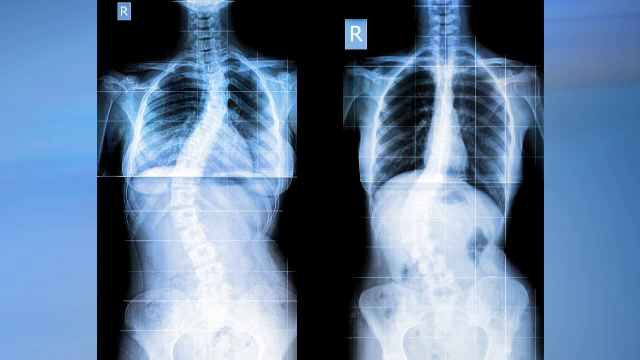

Tot mai mulți tineri români au probleme serioase la coloana vertebrală. Gimnastica medicală, soluția pentru durerile de spate